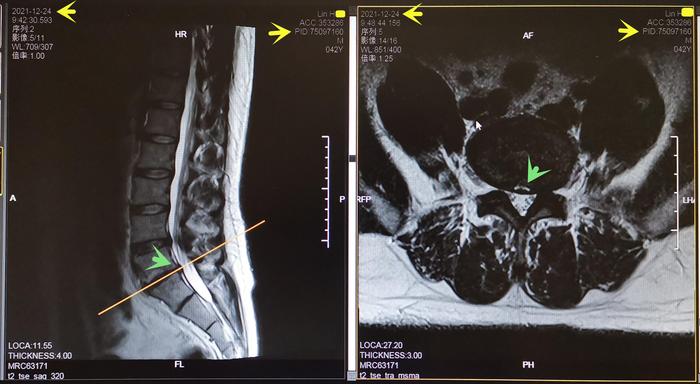

Lin先生,42岁,202011月腰及左下肢麻痛1月。此前反复发作左肩背、腰痛4年,急性发时不能起床,有一次用救护车送医院。检查身体:L5-S1间隙、左臀部及下肢压痛,左下肢腿抬高试验阳性,左踇背痛觉减退,左足背外侧痛觉减退,左踇背伸肌力减弱至3-4级,左跟腱反射减弱,神经受压损伤,诊断为“腰椎间盘突出症”。20201222日核磁共振:L5-S1椎间盘向左后外侧巨大突出,压迫神经根,见图7。建议患者微创治疗之后功能训练,患者拒绝手术治疗要求功能训练。经过每周13个月的训练后,患者的下肢麻痛基本消失,腰骶部疼痛明显减轻。又过2个月左下肢麻痛及不适消失。检查身体:左侧腰L5-S1轻压痛,双下肢直腿抬高试验恢复正常,左踇背痛、触觉基本恢复正常,双下肢肌力和生理反射恢复正常。20211224日复查腰椎核磁共振:L5-S1左侧突出的椎间盘基本消失,神经根受压解除,见图8。继续维持训练避免了复发加重,恢复工作生活,图9

图8. Lin先生2021年12月24日L5-S1椎间盘左侧突出消失,解除了神经根压迫,绿色箭头。

3. 腰椎间盘突出的消失:有效的专门的功能训练复健,促进椎间盘的消失,慢性腰痛消失而且突出的椎间盘消失。Lin先生就达到了这种理想效果,图8